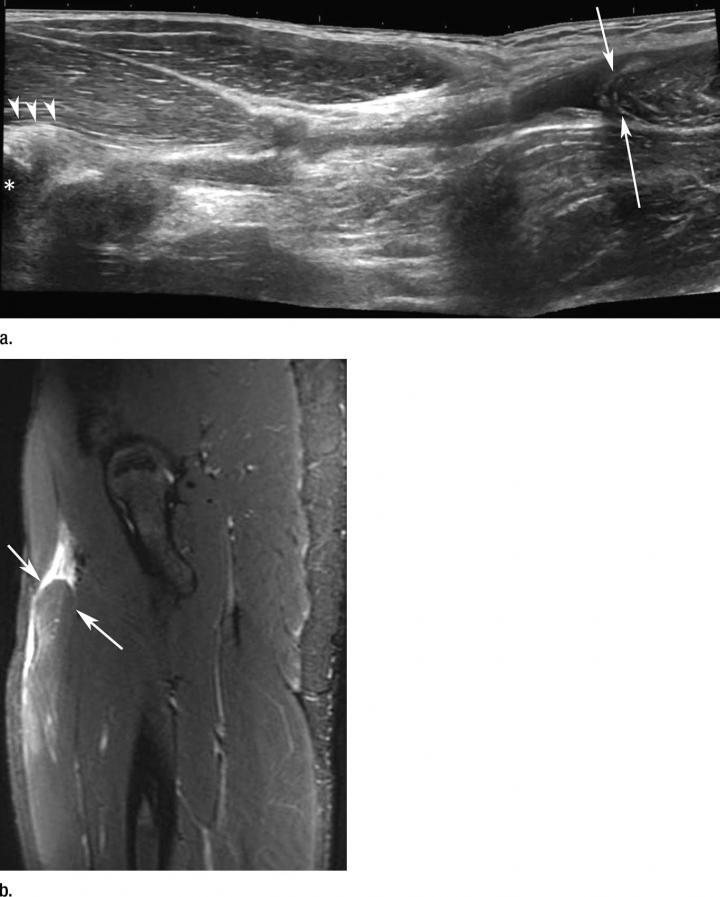

image: Images in a sprinter with acute anterior thigh pain sustained while training. (a) Ultrasound image of anterior thigh shows complete rupture of proximal rectus femoris muscle (arrowheads) with major distal retraction (arrows). Origin of proximal tendon (arrowheads) is located at anterior inferior iliac spine (?). (b) Fat-suppressed T2-weighted MR imaging demonstrates distal retraction of proximal rectus femoris muscle (arrows).